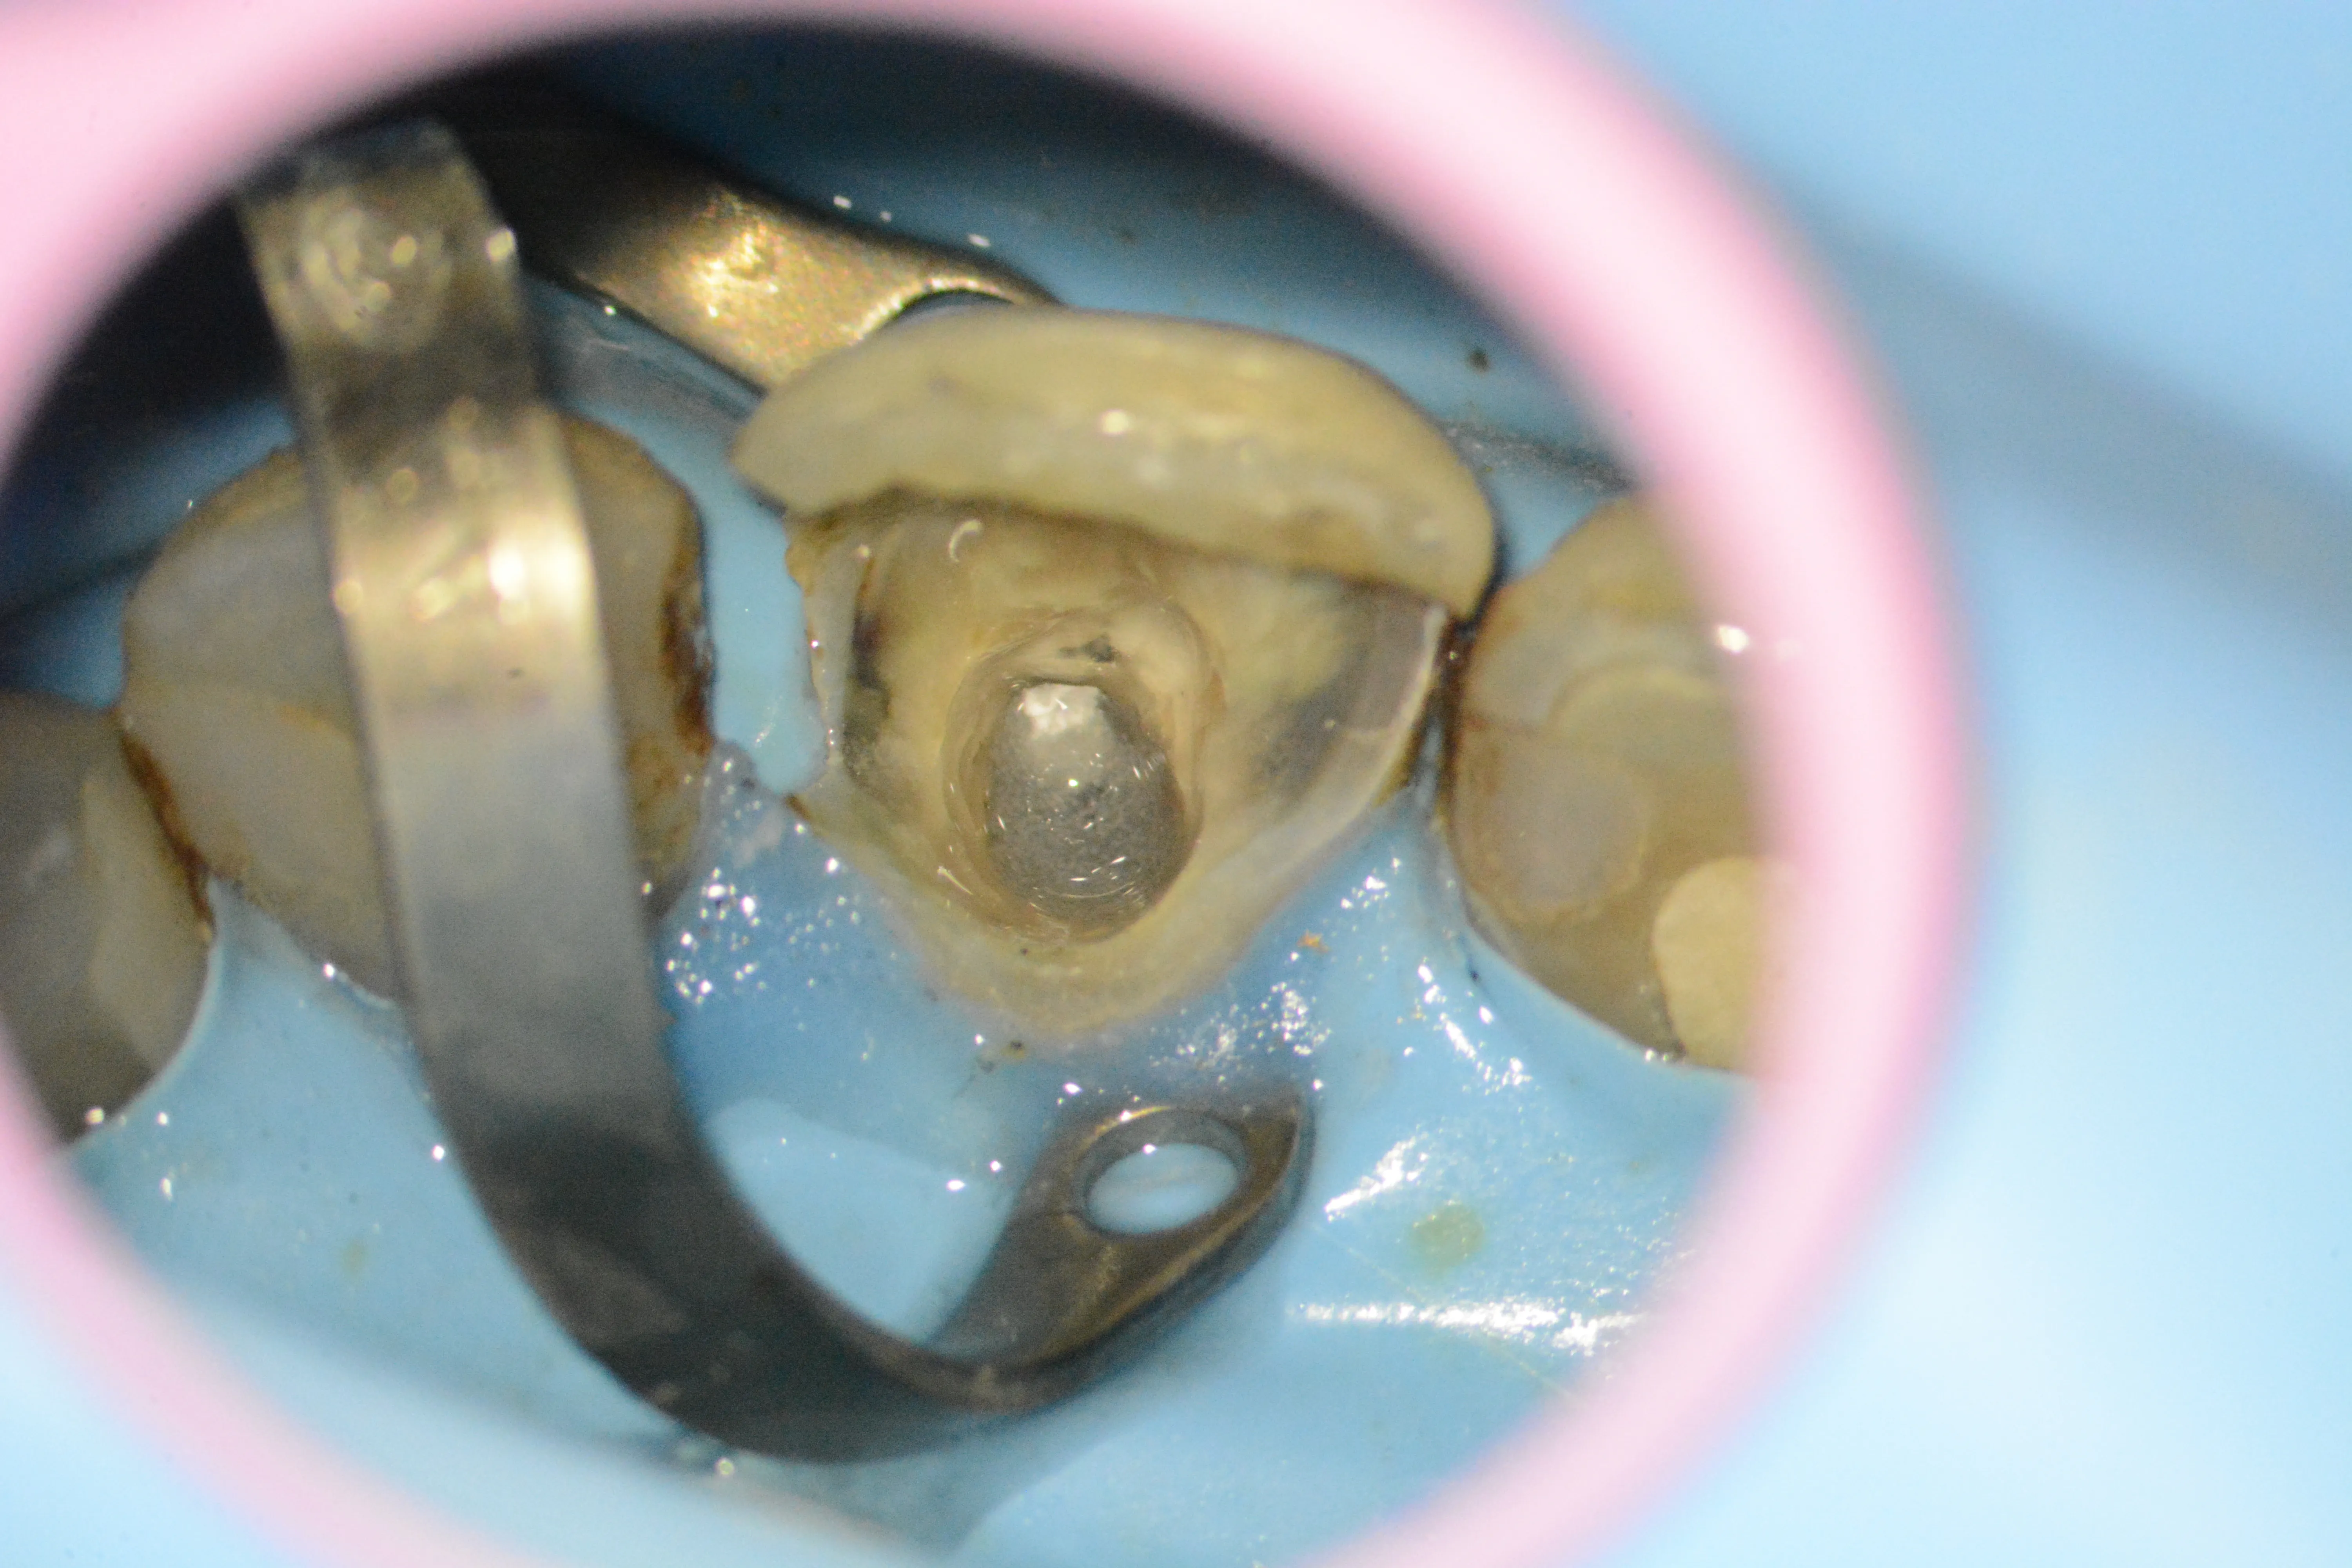

1 – Aspect clinic inițial